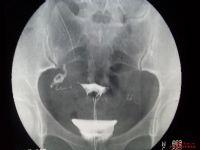

“現在有的家長已經迷信到了不顧孩子安危的地步,實在很不應該。”最近,廬江婦產科遇到這樣一對夫妻,她們特地請大師算了時辰,一定要在那個“吉時”把孩子剖出來。“家長之所以一定要選吉時,是因為他們覺得這一輩子就生這么一個孩子,出生的這一天決定了孩子一輩子的命運,所以非常看重。”家長跟婦產科專家說出了心里話,盡管專家一再勸說:“孩子剛過38周,雖然從理論上說38周-42周都算足月,但是,剛到38周的孩子,如果體重低的肺還不夠成熟,其他器官也沒有足月的好。”可惜,這對夫妻并不愿意妥協,結果,孩子剖出來后果然因為肺發育不成熟,在兒科住了10天,不得不用藥促進肺成熟,多花了錢不說,還讓寶寶受罪。這對夫妻很是后悔,但是卻沒話可說。

提前剖腹產,不但對新生兒有傷害,對媽媽的健康也是不利的,如果宮頸不夠成熟,不但容易大出血,而且惡露也不易排干凈。所以,專家提醒,那些有手術指征需要剖腹產的準媽媽,一定要根據自身的情況決定剖腹產的時間,而不是挑所謂的日子。能生一個健康聰明的寶寶才是第一位的,如果因為父母的愚昧無知給寶寶造成不必要的傷害,那將是無法彌補的!一切要以寶寶和媽媽的安全為前提考慮,沒有特殊不良狀況,醫生還是建議一切順其自然!